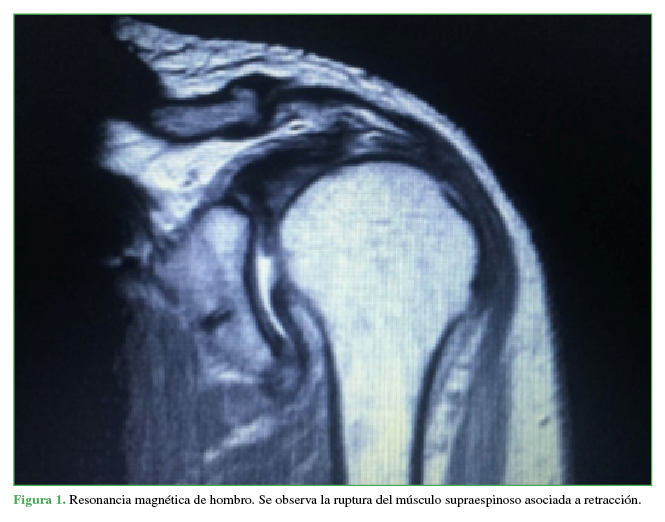

Lesión traumática del nervio axilar identificada luego de la reparación del manguito rotador. [Traumatic injury of the axillary nerve identified after rotator cuff repair]